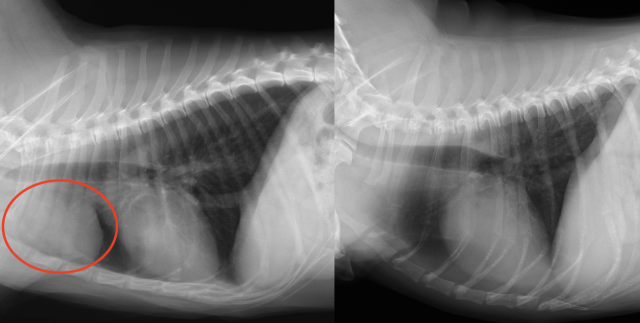

・レントゲン検査:大きさ、巨大食道症、肺炎、胸水貯留、遠隔転移(肺など)の評価

胸腺腫のレントゲン(左の赤丸、右は正常なレントゲン)